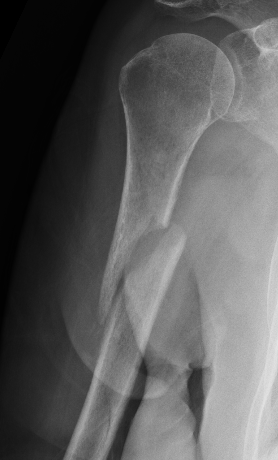

Holstein Lewis fracture

Holstein Lewis fractureHolstein Lewis

Holstein-Lewis JBJS Am 1963

- series of 7 oblique distal third fractures with radial nerve injury

- all were treated operatively

- nerve in fracture gap in 2 / impaled in 1 / severed in 2 / contused +/- in callus in 2

- advised against attempted closed reduction

- risk of contusing nerve between fragments

- advised early open reduction through anterolateral approach

- the radial nerve is closely assoicated with the fracture site and the fracture spike